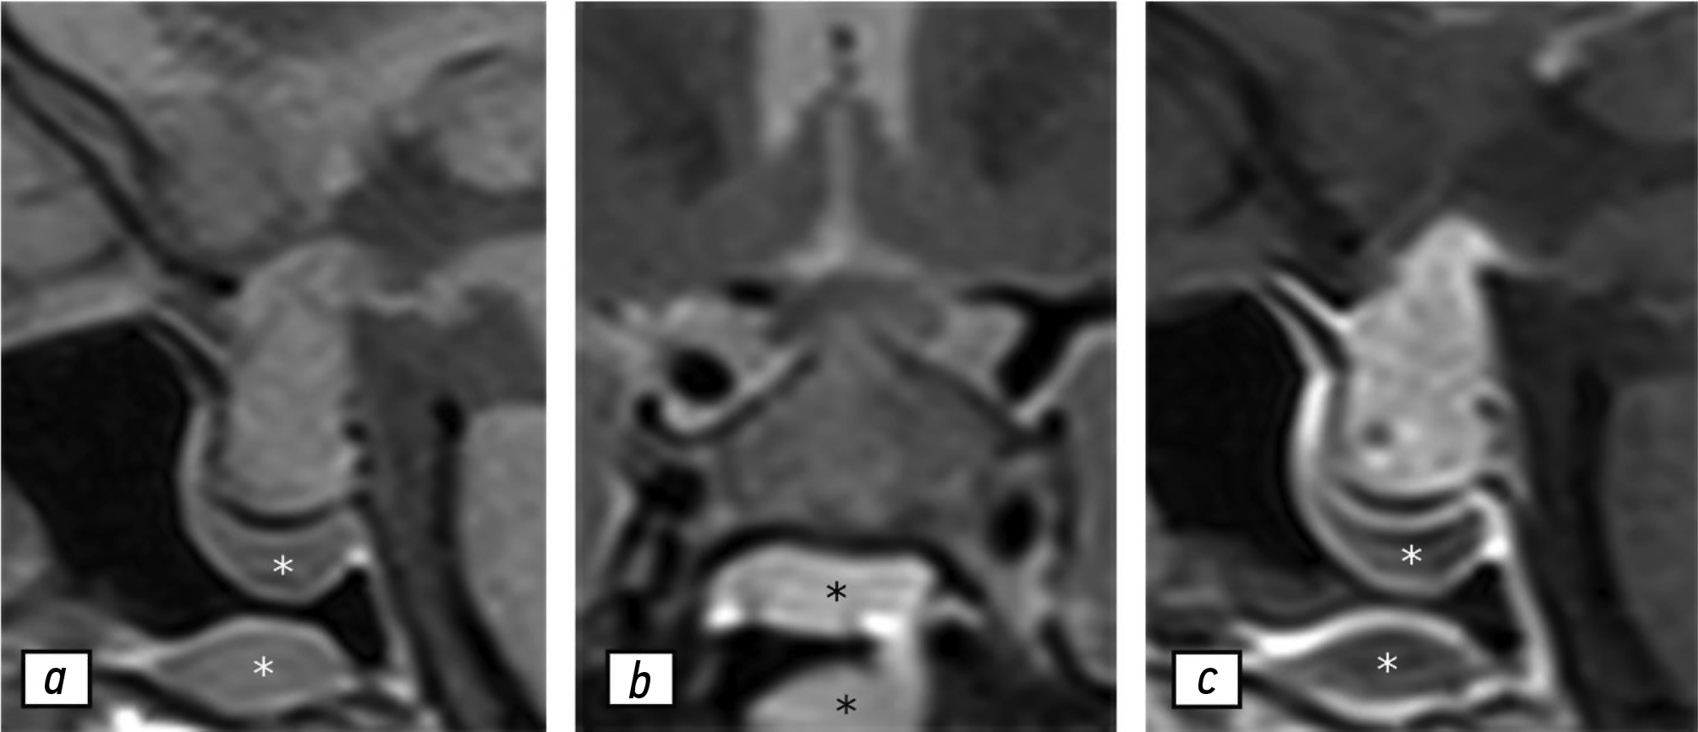

Результаты контрольной МРТ, выполненной в июле 2021 г., продемонстрировали увеличение гипофиза и усиление гетерогенности его структуры, что можно рассматривать как первые признаки гипофизита (рис. 2). В сентябре 2021 г. у пациентки не обнаружено каких-либо специфических симптомов, кроме головной боли. При проведении лабораторных исследований выявлено значимое снижение концентрации пролактина — 96,6 мМЕ/л.

Рис. 2. Результаты магнитно-резонансной томографии гипофиза, 09.07.2021: a — T1-взвешенное изображение в сагиттальной проекции; b — T2-взвешенное изображение в коронарной проекции; с — T1-взвешенное изображение в сагиттальной проекции с контрастированием. Отмечено умеренное увеличение гипофиза, усиление сигнала в его веществе (звёздочка) на T2-взвешенных изображениях (b), а также гетерогенное накопление контрастного вещества в центральной области гипофиза.

С учётом изменения гормонального статуса пациентки и ухудшения её состояния рекомендовано выполнение МРТ гипофиза (рис. 3). При её проведении не выявлено каких-либо значимых изменений его размера или структуры. Тем не менее отмечено резкое утолщение ножки гипофиза и хиазмы, а также усиление гетерогенности структуры. С целью коррекции гипотиреоза пациентке назначен левотироксин натрия — 25 мкг в сутки. Лечение каберголином продолжено с учётом ранее рекомендованной дозы. На фоне лечения пациентка отмечала усиление тошноты, головокружения и общую слабость.

Рис. 3. Результаты магнитно-резонансной томографии гипофиза, 04.02.2022: a — T1-взвешенное изображение в сагиттальной проекции; b — T2-взвешенное изображение в коронарной проекции; с — T1-взвешенное изображение в сагиттальной проекции с контрастированием. Отмечено прогрессирование очага, утолщение хиазмы (стрелки) и ножки гипофиза. Увеличение гипофиза и неоднородности его структуры наблюдали без выраженной динамики по сравнению с данными за 09.07.2021.